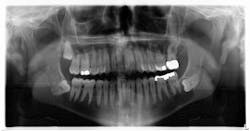

A healthy, 38-year-old male presented to the office for a comprehensive exam. His blood pressure was within normal limits, and no medications were being taken. Bitewing radiographs were taken, and it was noted that there was a cystlike lesion on what appeared to be a mesial impaction of no. 17. A panoramic radiograph indeed revealed a large, radiolucent/cystlike lesion surrounding a mesial/inferior-positioned no. 17. The widest point of the cyst measured approximately 3 cm. The patient reported knowing about the lesion but was not inclined to have it removed because it was not bothering him. The area was not tender to palpation; tooth no. 18 had normal pocketing and tested normal to cold, percussion, and bite.

Dentigerous cyst. A dentigerous cyst is “an odontogenic cyst that surrounds the crown of an impacted tooth, caused by fluid accumulation between the reduced enamel epithelium and enamel surface, resulting in a cyst in which the crown is located within the lumen and root(s) outside.”1 Typically, dentigerous cysts remain asymptomatic, but large growths have been known to produce swelling and pain. The most common teeth involved are the unerupted maxillary and mandibular third molars or maxillary cuspids.1 The highest incidence occurs during the second and third decades of life.2 The recommended treatment is complete enucleation, which reduces the possibility of potentially dangerous cells remaining in the region after surgery to form residual cysts, ameloblastomas, or other lesions.2